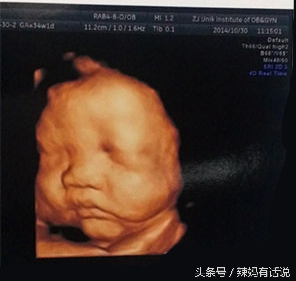

顺便还帮我拍了宝宝的脸,肉肉的!都说像他爸爸啊!